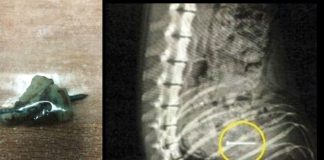

Beštiálna penzistka (61) hádzala psom v parku maškrty napichané klincami! Policajti...

Staršia žena z Dunajskej Stredy neznášala psov. Preto sa ich celé tri mesiace pokúšala zabíjať nebezpečnými návnadami! Do kusov slaniny a kuracieho mäsa zapichovala...